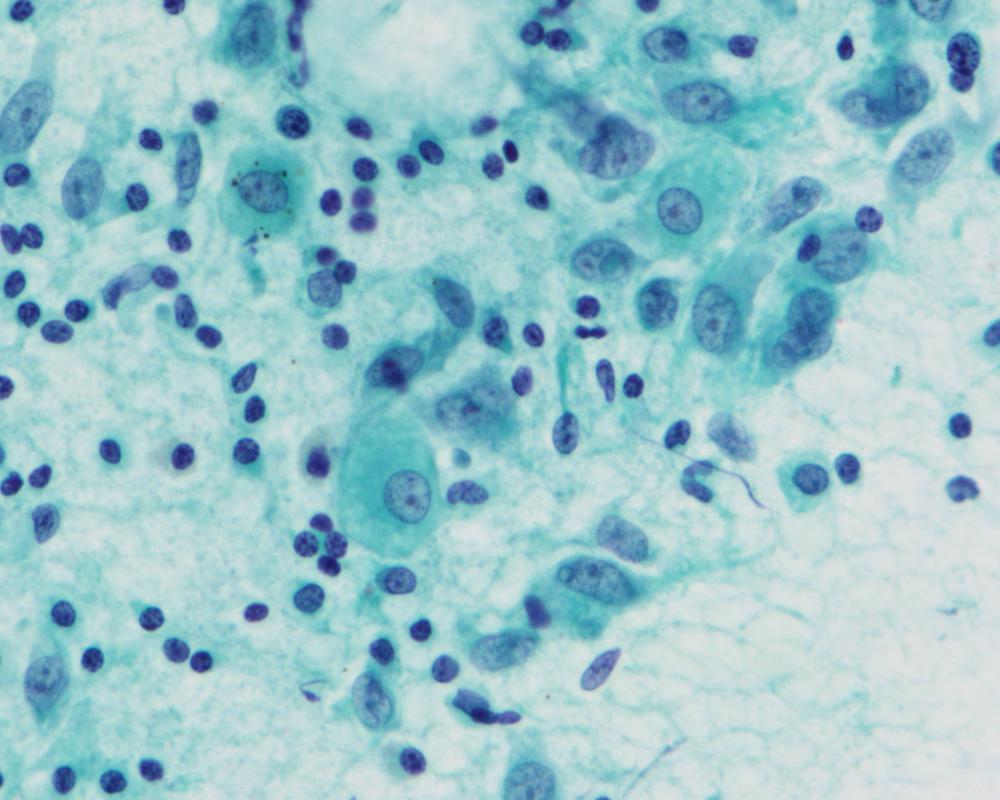

第36回日本臨床細胞学会九州連合会学会(大分)スライドカンファレンス症例5

種別:消化器・口腔

出題:九州歯科大学 健康増進学講座 口腔病態病理学分野 矢田 直美

| 年齢 | 70歳代 | 性別 | 男性 |

| 採取部位 | 口底部 | 採取方法 | 歯間ブラシ擦過 |

| 検体処理法 | 従来法,LBC法 (ThinPrep) |

臨床所見

既往歴:前立腺癌(10年前),高血圧症,逆流性食道炎

現病歴:かかりつけ内科医に口底部腫瘤を指摘され受診となった。初診時,舌下小丘すぐ横に10×10mmの軽度硬結を触れる腫瘤を認めたため,擦過細胞診が行われた。

| 正解 | 3.類基底扁平上皮癌 |

▼選択肢及び投票結果

| 1.上皮内癌 | 1件 | (1.6%) | |

| 2.高分化型扁平上皮癌 | 7件 | (10.9%) | |

| 3.類基底扁平上皮癌 | 36件 | (56.2%) | |

| 4.粘表皮癌 | 14件 | (21.9%) | |

| 5.腺癌 (前立腺癌の転移) | 6件 | (9.4%) | |

| 投票総数 | 64件 | (100%) |